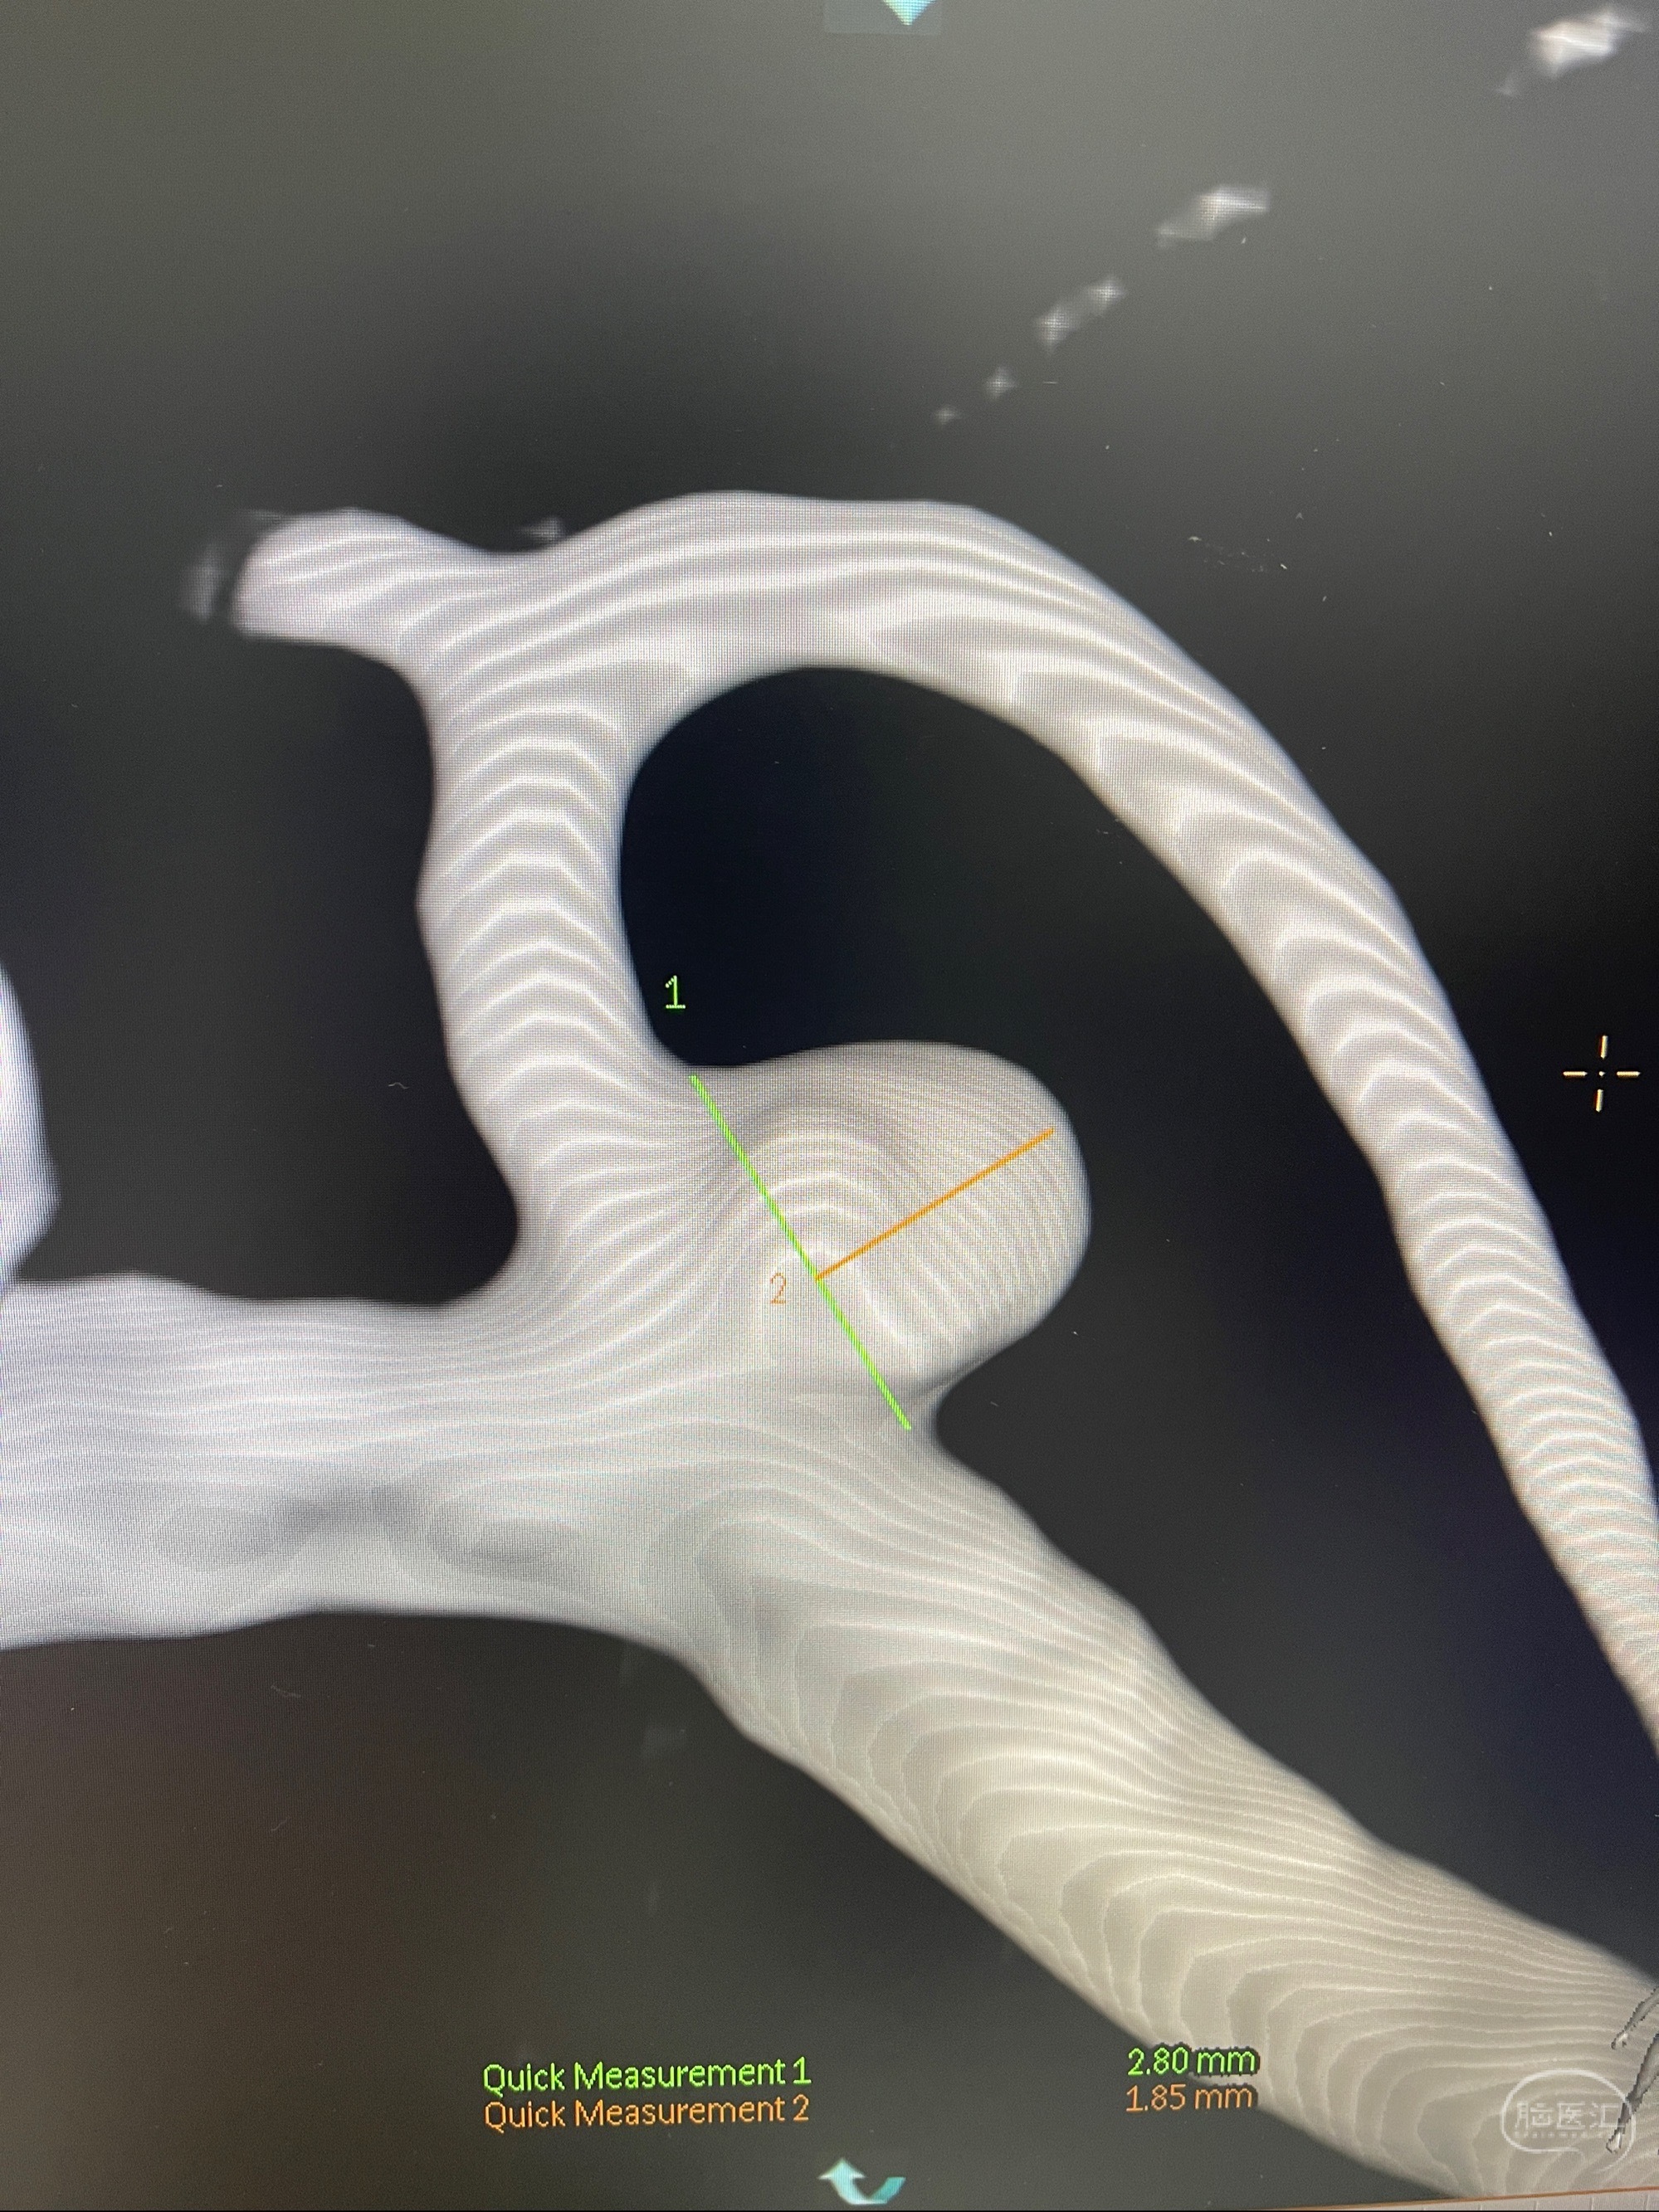

辅助检查:2023-07-12 上海大学附属第三医院 头颅CTA:左侧大脑中动脉M1段动脉瘤(1.7*3.4mm),右侧大脑前动脉A1段缺如,左侧椎动脉V4段纤细。

左侧大脑中动脉动脉瘤,约2.6-2.8-3.4-2mm大小(瘤颈部、瘤体部、瘤高)

1.左侧大脑中动脉动脉瘤,约2.6-2.8-3.4-2mm大小(瘤颈部、瘤体部、瘤高)